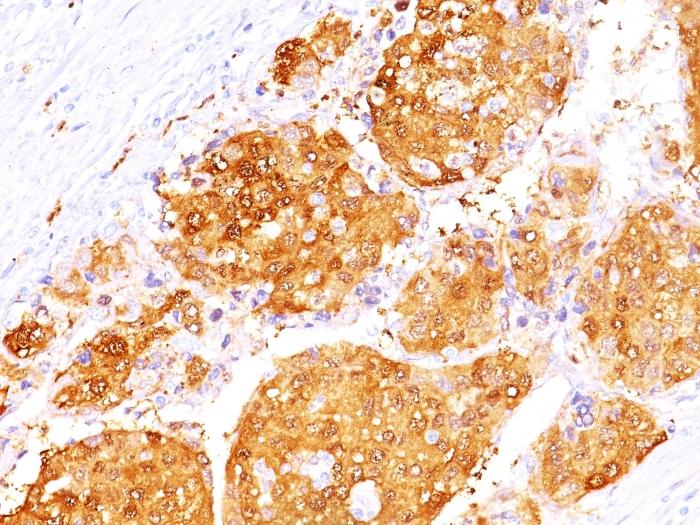

This antibody recognizes a protein of 35-38 kDa, which is identified as Arginase 1 (ARG1). Arginase is a manganese metallo-enzyme that catalyzes the hydrolysis of arginine to generate ornithine and urea. Arginase I and II are isoenzymes which differ in subcellular localization, regulation, and possibly function. Arginase I is a cytosolic enzyme, which is expressed mainly in the liver as part of the urea cycle, whereas arginase II is a mitochondrial protein found in a variety of tissues. Antibodies to Arginase 1 label hepatocytes in normal tissues and granulocytes in peripheral blood. Arginase 1 is a sensitive and specific marker for identification of hepatocellular carcinoma.Primary antibodies are available purified, or with a selection of fluorescent CF® Dyes and other labels. CF® Dyes offer exceptional brightness and photostability. Note: Conjugates of blue fluorescent dyes like CF®405S and CF®405M are not recommended for detecting low abundance targets, because blue dyes have lower fluorescence and can give higher non-specific background than other dye colors.

Positive Control

293T cells. Hepatocellular Carcinoma (HCC).

Cytoplasmic

Cell tissue expression

IHC, FFPE (verified)

IHC (FFPE) (verified)